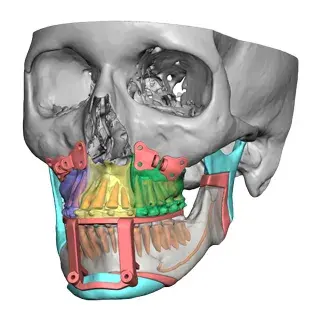

3D Systems' VSP® surgical planning solutions for craniomaxillofacial (CMF) applications received FDA clearance as a service-based approach to personalized surgery over 10 years ago.

3D Systems and Stryker Corporation have partnered to provide surgeons with best-in-class products and services for craniomaxillofacial surgeries. As a leader in personalized healthcare solutions, 3D Systems has planned and delivered devices for more than 140,000 patient-specific cases. The Stryker Craniomaxillofacial business specializes in providing patient-specific options and innovative solutions that help drive efficiencies in surgical suites. The combination of Stryker’s specialized team and advanced implants with 3D Systems' cutting-edge 3D printing technologies and expert consulting services positions both companies to provide a superior level of service to healthcare professionals who use these revolutionary solutions.